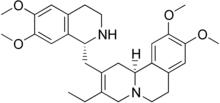

Dehydroemetine is a synthetically produced antiprotozoal agent similar to emetine in its anti-amoebic properties and structure (they differ only in a double bond next to the ethyl substituent), but it produces fewer side effects. In the United States, it is manufactured by Roche.

| Formula | C29H38N2O4 |

| Molar mass | 478.633 g·mol−1 |